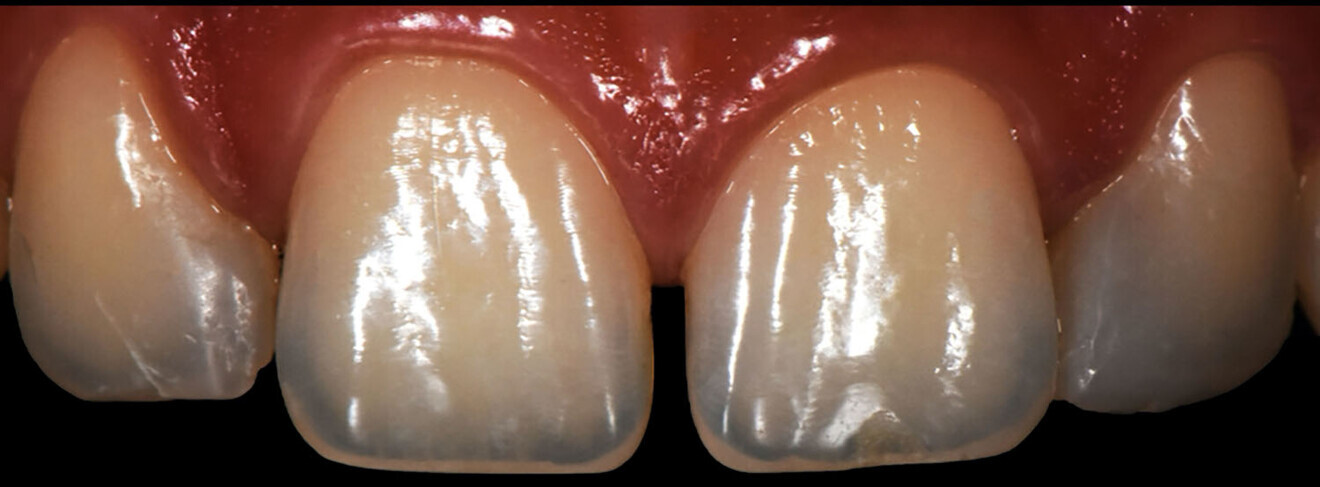

Record taking and diagnosis On clinical examination, there were no signs of structural impairment related to previous treatments. On radiographic examination of the crowns, pulps, roots and periodontium, there were no findings. The diagnosis was a diastema between teeth #11 and 21 and minimal gap between teeth #12 and 11.

Treatment plan The adhesive technique consisted of the two-matrix technique for diastema closure between teeth #11 and 21 and the transparent-matrix technique for closure of the space between teeth #12 and 11. A nano-hybrid composite, in combination with a universal adhesive, was used as the material for the gap closures. For spaces < 1.5 mm, it is recommended to restore freehand (like in this case), whereas for gaps > 1.5 mm, it is advisable to use a silicone key to achieve proportional tooth widths and an aesthetic result (Fig. 1).

The Digital Smile Design (DSD) visual technology (DSD Planning Center) for a thorough analysis based on the proportions between the teeth was used. The patient was shown the new geometric lines of the planned restorations.

We followed a thorough analysis of the chromatic spectrum, as described by Naorungroj, to accurately and precisely establish the shades to be used in the operative steps (Fig. 2).1 The photographic material was carefully analysed to determine the ideal work planes to gain the information required to achieve the ultimate aesthetic aim of the treatment.